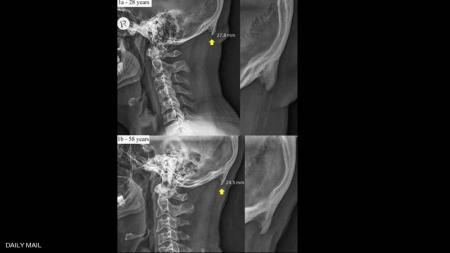

وبحسب ما نقلت صحيفة "ديلي ميل" البريطانية، فإن الشخص الذي يكثر من استخدام الهاتف الذكي، يظهر لديه ما يشبه شوكة عظمية في الجهة الخلفية من جمجمة الرأس، بسبب الانحناء والتركيز في شاشة الجهاز.

وتوضح الدراسة التي جرى إعدادها في جامعة "سان شان كوست" الأسترالية، أن جمجمة الإنسان أضحت تحدث هذه "الشوكة العظمية" بشكل متزايد.

وبوسع الكثيرين في الوقت الحالي أن يتحسسوا هذه الشوكة في مؤخرة الرأس، أما الأشخاص الصلع فيمكن رصدها بسهولة في رؤوسهم.